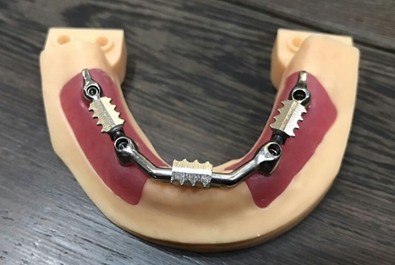

毛國(guó)斌種植病例——群討論分享